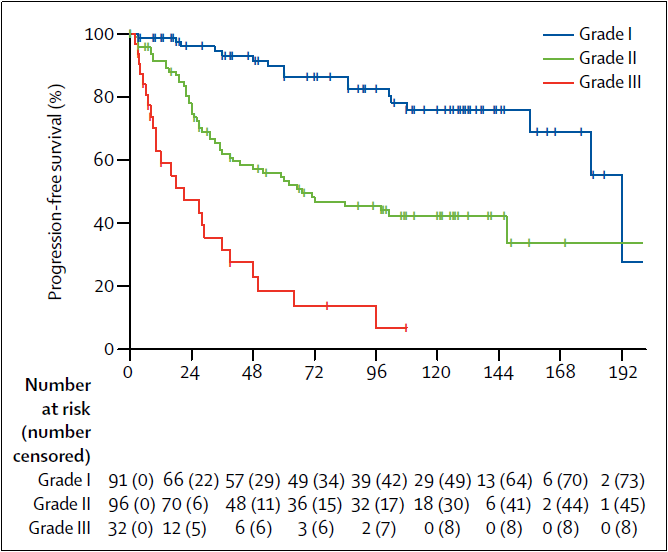

世界卫生组织(WHO)分类方案根据显微镜下的细胞类型将脑膜瘤分成15种组织亚型。这些组织学亚型分为三个等级(WHO I-III级),组织分型通常根据细胞学特征反映肿瘤生长速率和复发的可能性。非典型脑膜瘤(WHO II级,占脑膜瘤病例的18%)表现出组织和细胞异常增加。这些肿瘤的生长速度快于良性脑膜瘤,通常以脑部侵袭为特征。非典型脑膜瘤比良性脑膜瘤(WHO I级)复发的可能性更高。恶性脑膜瘤(WHO III级)显示细胞异常增加,并且比良性和非典型脑膜瘤的生长速度更快。恶性脑膜瘤比其他两种亚型更容易侵袭大脑并且复发频率更高。

脑膜瘤分子分型:脑膜瘤是常见的颅内原发性脑肿瘤,当前脑肿瘤的诊断模式是组织型和基因型的整合诊断。虽然目前脑膜瘤的诊断仍然引用传统的组织分型,但是分子检测在脑膜瘤瘤诊断和预后评估中的作用越来越大,尤其是检测复发相关的分子标志物。关于脑膜瘤分子分型的研究越来越趋于成熟,近期在柳叶刀肿瘤学期刊中发表了脑膜瘤6亚型的分子分型研究,其中恶性脑膜瘤通常携带有NF2,TERT基因启动子激活突变,CDKN2A基因缺失,1p和10号染色体缺失等分子特征。